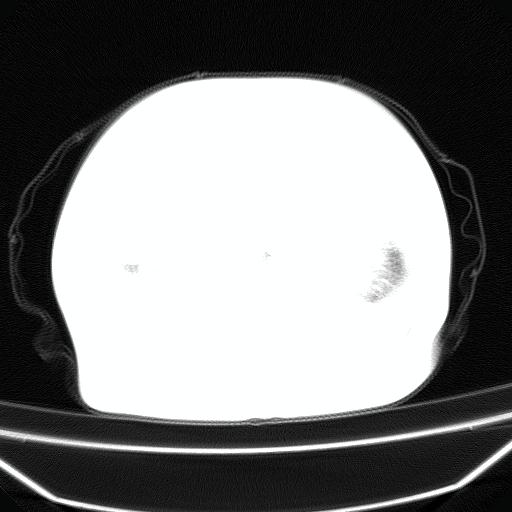

以下是引用liuyue在2008-4-19 22:25:00的发言:[br]先考虑:1.心衰伴肺水肿、双侧胸腔积液、叶间积液、双下肺不完全性肺不张; [br] 2.冠状动脉粥样硬化。

以下是引用lijuanln在2008-4-19 23:05:00的发言:[br]两侧胸腔积液,肺水肿[br]心包积液[br]提示心衰

以下是引用jiangjing在2008-4-20 10:43:00的发言:[br]结合病史支持 冠心病[冠状动脉钙化],心功能不全,肺淤血、肺水肿,双侧胸腔与斜裂积液